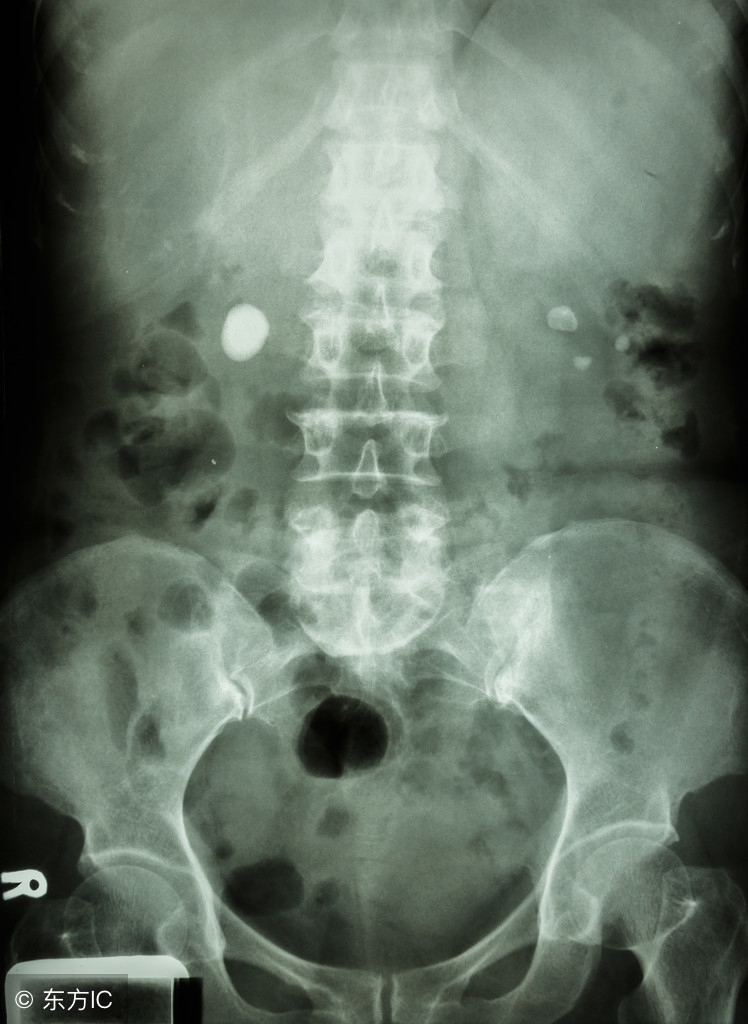

尿结石的检查

后尿结石可经直肠指检触及,前尿结石可直接沿尿道体表处扪及,用尿道探条经尿道探查时可有摩擦音及碰击感。X线平片可明确结石部位、大小及数目。尿道造影更能明确结石与尿道的关系,尤其对尿道憩室内的结石诊断更有帮助。